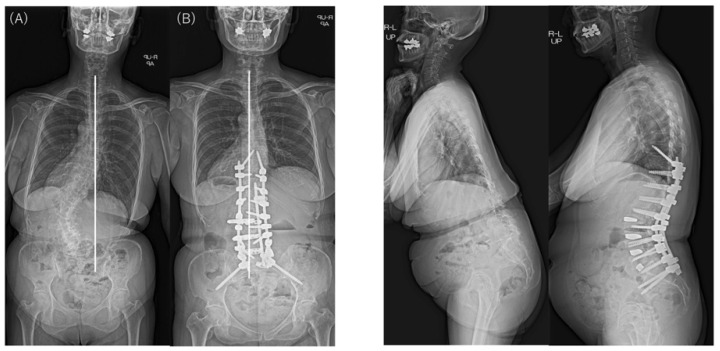

In the examination of the radiographic sagittal parameters across the entire cohort, we found significant improvements in PI–LL, including SVA, LL, and PT. However, TK and PJA increased postoperatively. The major Cobb angle was corrected markedly from 48.8° preoperatively to 13.2° postoperatively (p < 0.001). L4 coronal tilt improved significantly from 18.6° preoperatively to 8.7° postoperatively (p < 0.001) and L5 coronal tilt from 12.9° preoperatively to 7.3° postoperatively (p < 0.001). The major Cobb angle and L4 and L5 coronal tilts also improved in both groups. However, the L4 and L5 coronal tilt were larger before and after surgery in the Obeid type 2 group than in the Obeid type 1A group. The │CBD│ did not differ significantly between the type 1A and type 2A groups before and after surgery. In patients with Obeid type 1A, the │CBD│ changed from 78.4 mm before to 22.8 mm after surgery (p < 0.001). In patients with Obeid type 2A, the change in the │CBD│ from 46.9 mm to 38.5 mm was not significant (p = 0.506) (Table 3).

Analysis of the change or correction (Δ) for each spinal parameter showed a significant difference in ΔTK for the sagittal parameter TK. ΔTK was larger in patients with Obeid type 2A, but other sagittal parameters did not differ significantly between groups. Δ│CBD│ was significantly larger in patients with Obeid type 1A than those with Obeid type 2A (76.6 mm vs. 24.1 mm; p < 0.001) (Table 4).

There were no significant intergroup differences in the changes in the major Cobb angle, correction of coronal tilts of L4 and L5, and the PJA (Table 4). CM was found in 29 of 34 patients with SRS–Schwab type L ASD preoperatively and remained in 12 of these patients at the final follow-up. At the final follow-up, 58.6% (17/29) of patients with SRS–Schwab type L CM showed improvement in CM after corrective fusion using LLIF. Although the difference was not statistically significant, CM improved in 69.6% of patients with Obeid type 1A CM but only 16.7% of those with Obeid type 2A CM (p = 0.056) (Table 5).

Typical postoperative changes are shown in Figure 2, Figure 3 and Figure 4.

All patients received LLIF as the spinal correction surgery in this study. In the sagittal plane, it was suggested that CM types did not affect SRS–Schwab assessment factors ΔSVA, ΔPT, and ΔPI-LL. LLIF and posterior corrective fusion corrected the preoperative CM in nearly 70% of patients with Obeid type 1A. However, using LLIF to correct the CM deformity in the coronal plane in a patient with Obeid type 2A may worsen the main lumbar curve by causing malalignment toward the convex side (Figure 5 and Figure 6).